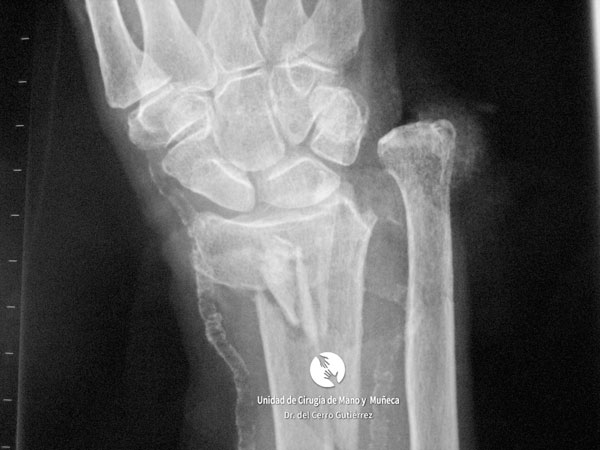

Imágenes de diagnótico de fracturas del radio distal de la muñeca

Las imágenes de diagnóstico son fundamentales para evaluar las fracturas del radio distal, identificar su gravedad y definir el tratamiento más adecuado. A continuación, presentamos una serie de ejemplos que muestran diferentes tipos de fracturas.

Fractura del Radio. Conminuta y Articular.